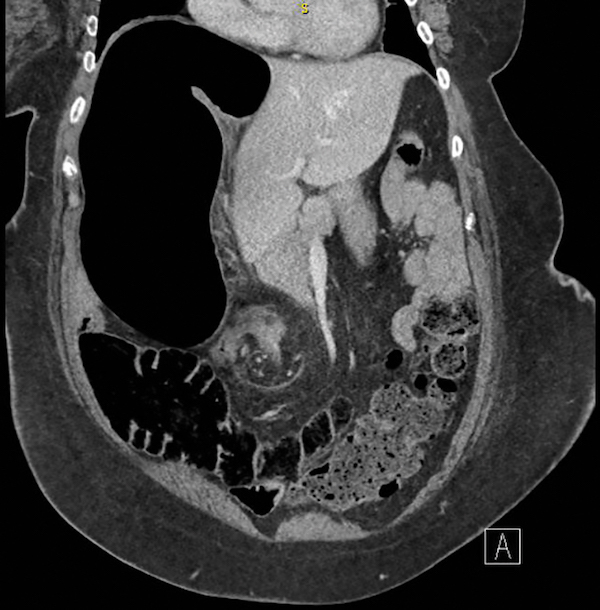

A 58-year-old woman presents to the emergency department (ED) with abdominal pain and distension. She has a history of spina bifida with a neurogenic bladder and chronic constipation, for which she takes an osmotic laxative on a daily basis. She has noted increasing abdominal pain for the week prior to presentation, and she has not passed any stool or gas for 4 days. She reports that she has had progressive abdominal distension and discomfort today, and now has nausea and vomiting, prompting evaluation. On exam, she is morbidly obese, has decreased bowel sounds, and tenderness throughout her abdomen, without guarding or rebound. Rectal examination reveals no palpable stool in the rectal vault. A computed tomography (CT) scan is done in the ED, with the results shown in the figure. Which of the following is the most likely diagnosis?

This woman’s CT scan reveals a sigmoid volvulus, as evident by twisting displacement of the base of the sigmoid colon and mesentery, leading to significant upstream dilation of her colon, with her right colon measuring >15 cm in maximal dimension. Sigmoid volvulus is uncommon, and only accounts for 3-5% of intestinal obstructions, and patients tend to be older with chronic constipation who are institutionalized or have cognitive issues. Management includes urgent endoscopic detorsion, which can help to untwist the colon, and allows removal of air from the proximal distended colon with placement of a decompression tube, with a success rate of 60-80%. Surgery is often performed for patients after the colon has been decompressed in order to prevent recurrence, which is seen in up to 90% of patients. Although a colonic malignancy could cause a mechanical large bowel obstruction, the twisted appearance on the mid pelvis is more suggestive of a volvulus. There is no evidence of free air on the CT scan, so perforation is unlikely. The clinical and radiographic features are not typical for diverticulitis or ileus.